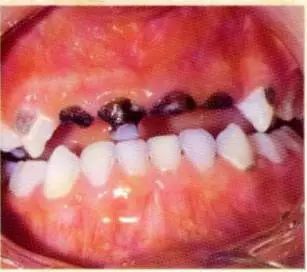

还有一张更震惊的

来自一位5岁孩子的口腔图

这只是噩梦的开始。

这样的牙齿还会引发更严重的牙齿问题。

蛀牙细菌感染扩散成间隙感染,

整个上唇部,面部肿起来。

甚至会影响生命。